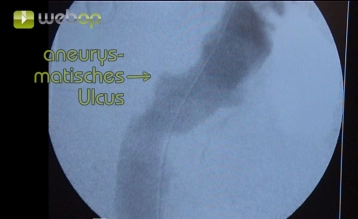

No artigo, é demonstrada a exclusão endoluminal de uma úlcera ateromatosa penetrante (PAU, excêntrica 32 x 24 mm) da aorta descendente. Devido a duas operações cirúrgicas vasculares anteriores na virilha esquerda e arteriosclerose grave, é realizada uma exposição extraperitoneal da artéria ilíaca externa.

Para um diâmetro ou profundidade da úlcera de ≥ 20 mm, o tratamento endovascular eletivo é indicado. Em casos de sinais de ruptura iminente (dor, sangue extra-aórtico), o tratamento endovascular é urgente. A dor é mencionada como um dos principais critérios para intervenção cirúrgica urgente.